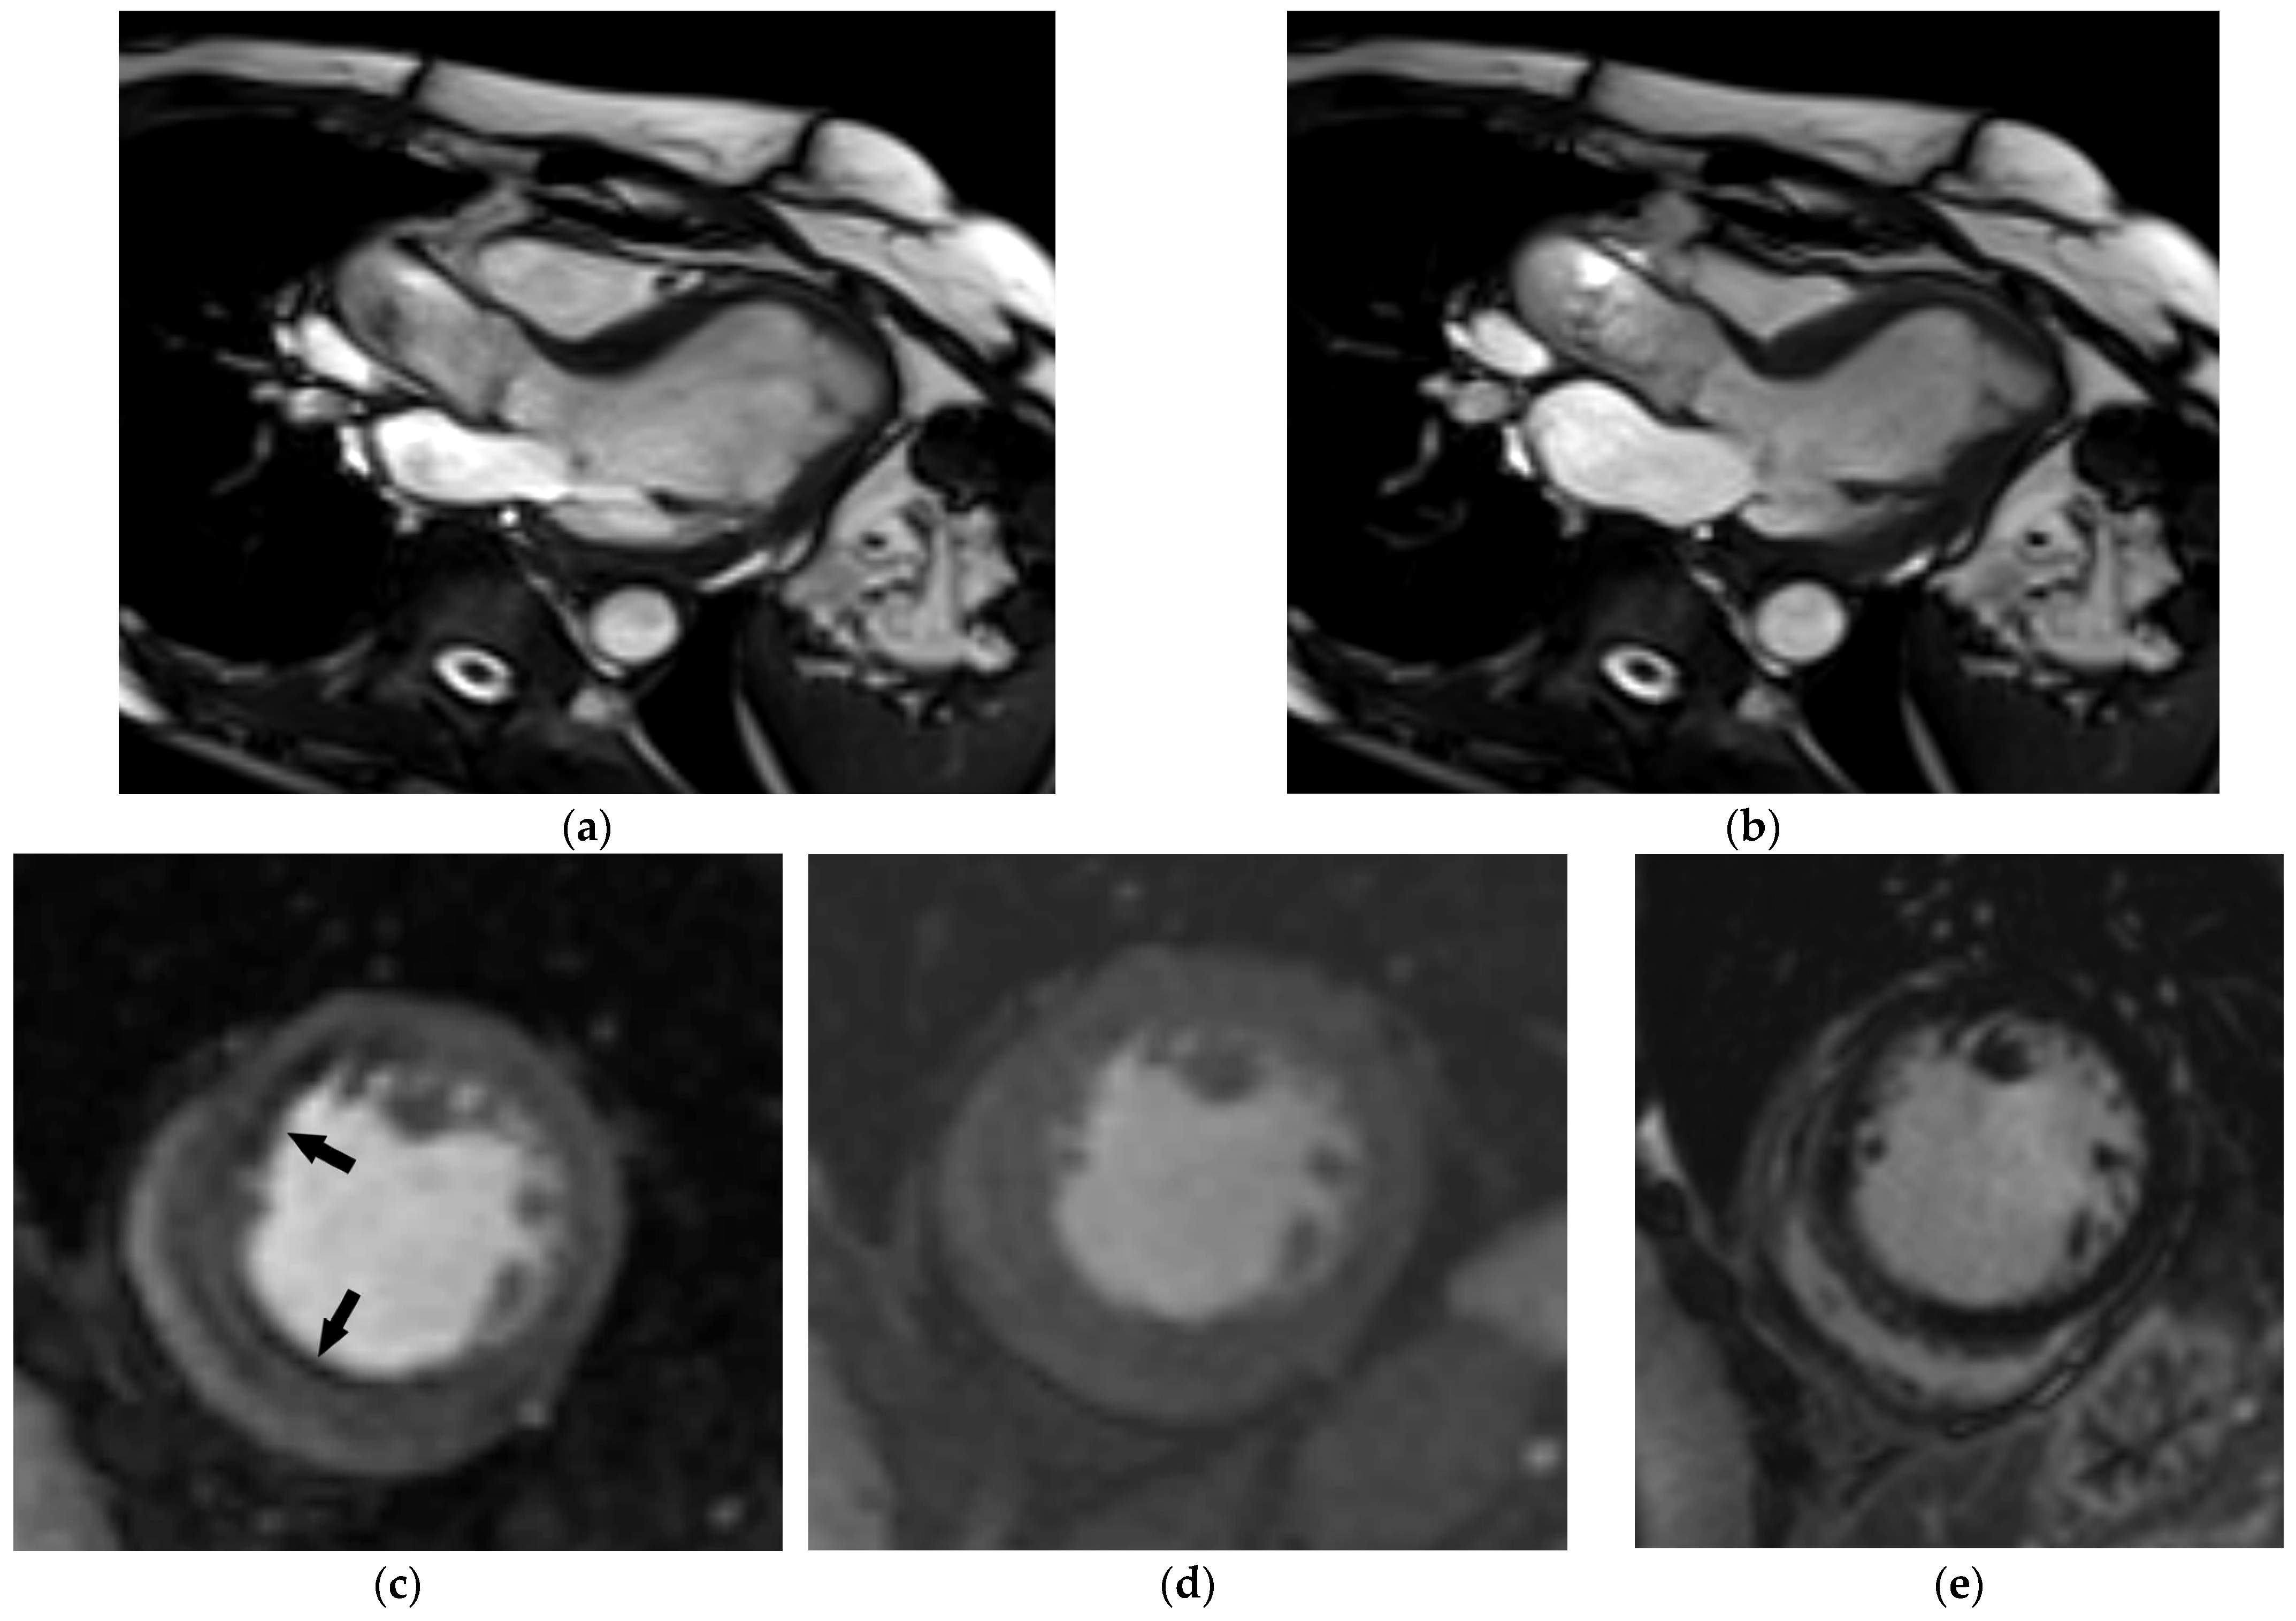

5.3. Magnetic Resonance Imaging

| Myocardial fibrosis | MRI tissue characterization required: prolonged myocardial T1 relaxation time, increased myocardial extracellular volume, late gadolinium enhancement |

| Coronary artery disease | CT: coronary artery calcification, coronary artery plaques with or without high-risk features, coronary artery stenosis |

| MRI: myocardial ischemia (stress testing), regional wall motion abnormalities (cine imaging), ischemic pattern of late gadolinium enhancement |

| Magnetic resonance imaging | Cardiac morphology and function Aortic morphology and stiffness (pulse wave velocity, aortic strain, and distensibility) | Imaging modality of choice for advanced assessment of cardiac morphology and function Non-invasive myocardial ischemia testing (stress test) Commonly used for follow-up of aortic diseases (especially in children and younger individuals) | Non-invasive myocardial tissue characterization Image acquisition in any desired plane The gold standard for assessment of myocardial mass, ventricular volumes, and ejection fraction | High costs Limited availability Long-lasting examinations Contraindications (ferromagnetic foreign bodies, non-conditional cardiac implantable electronic devices) |